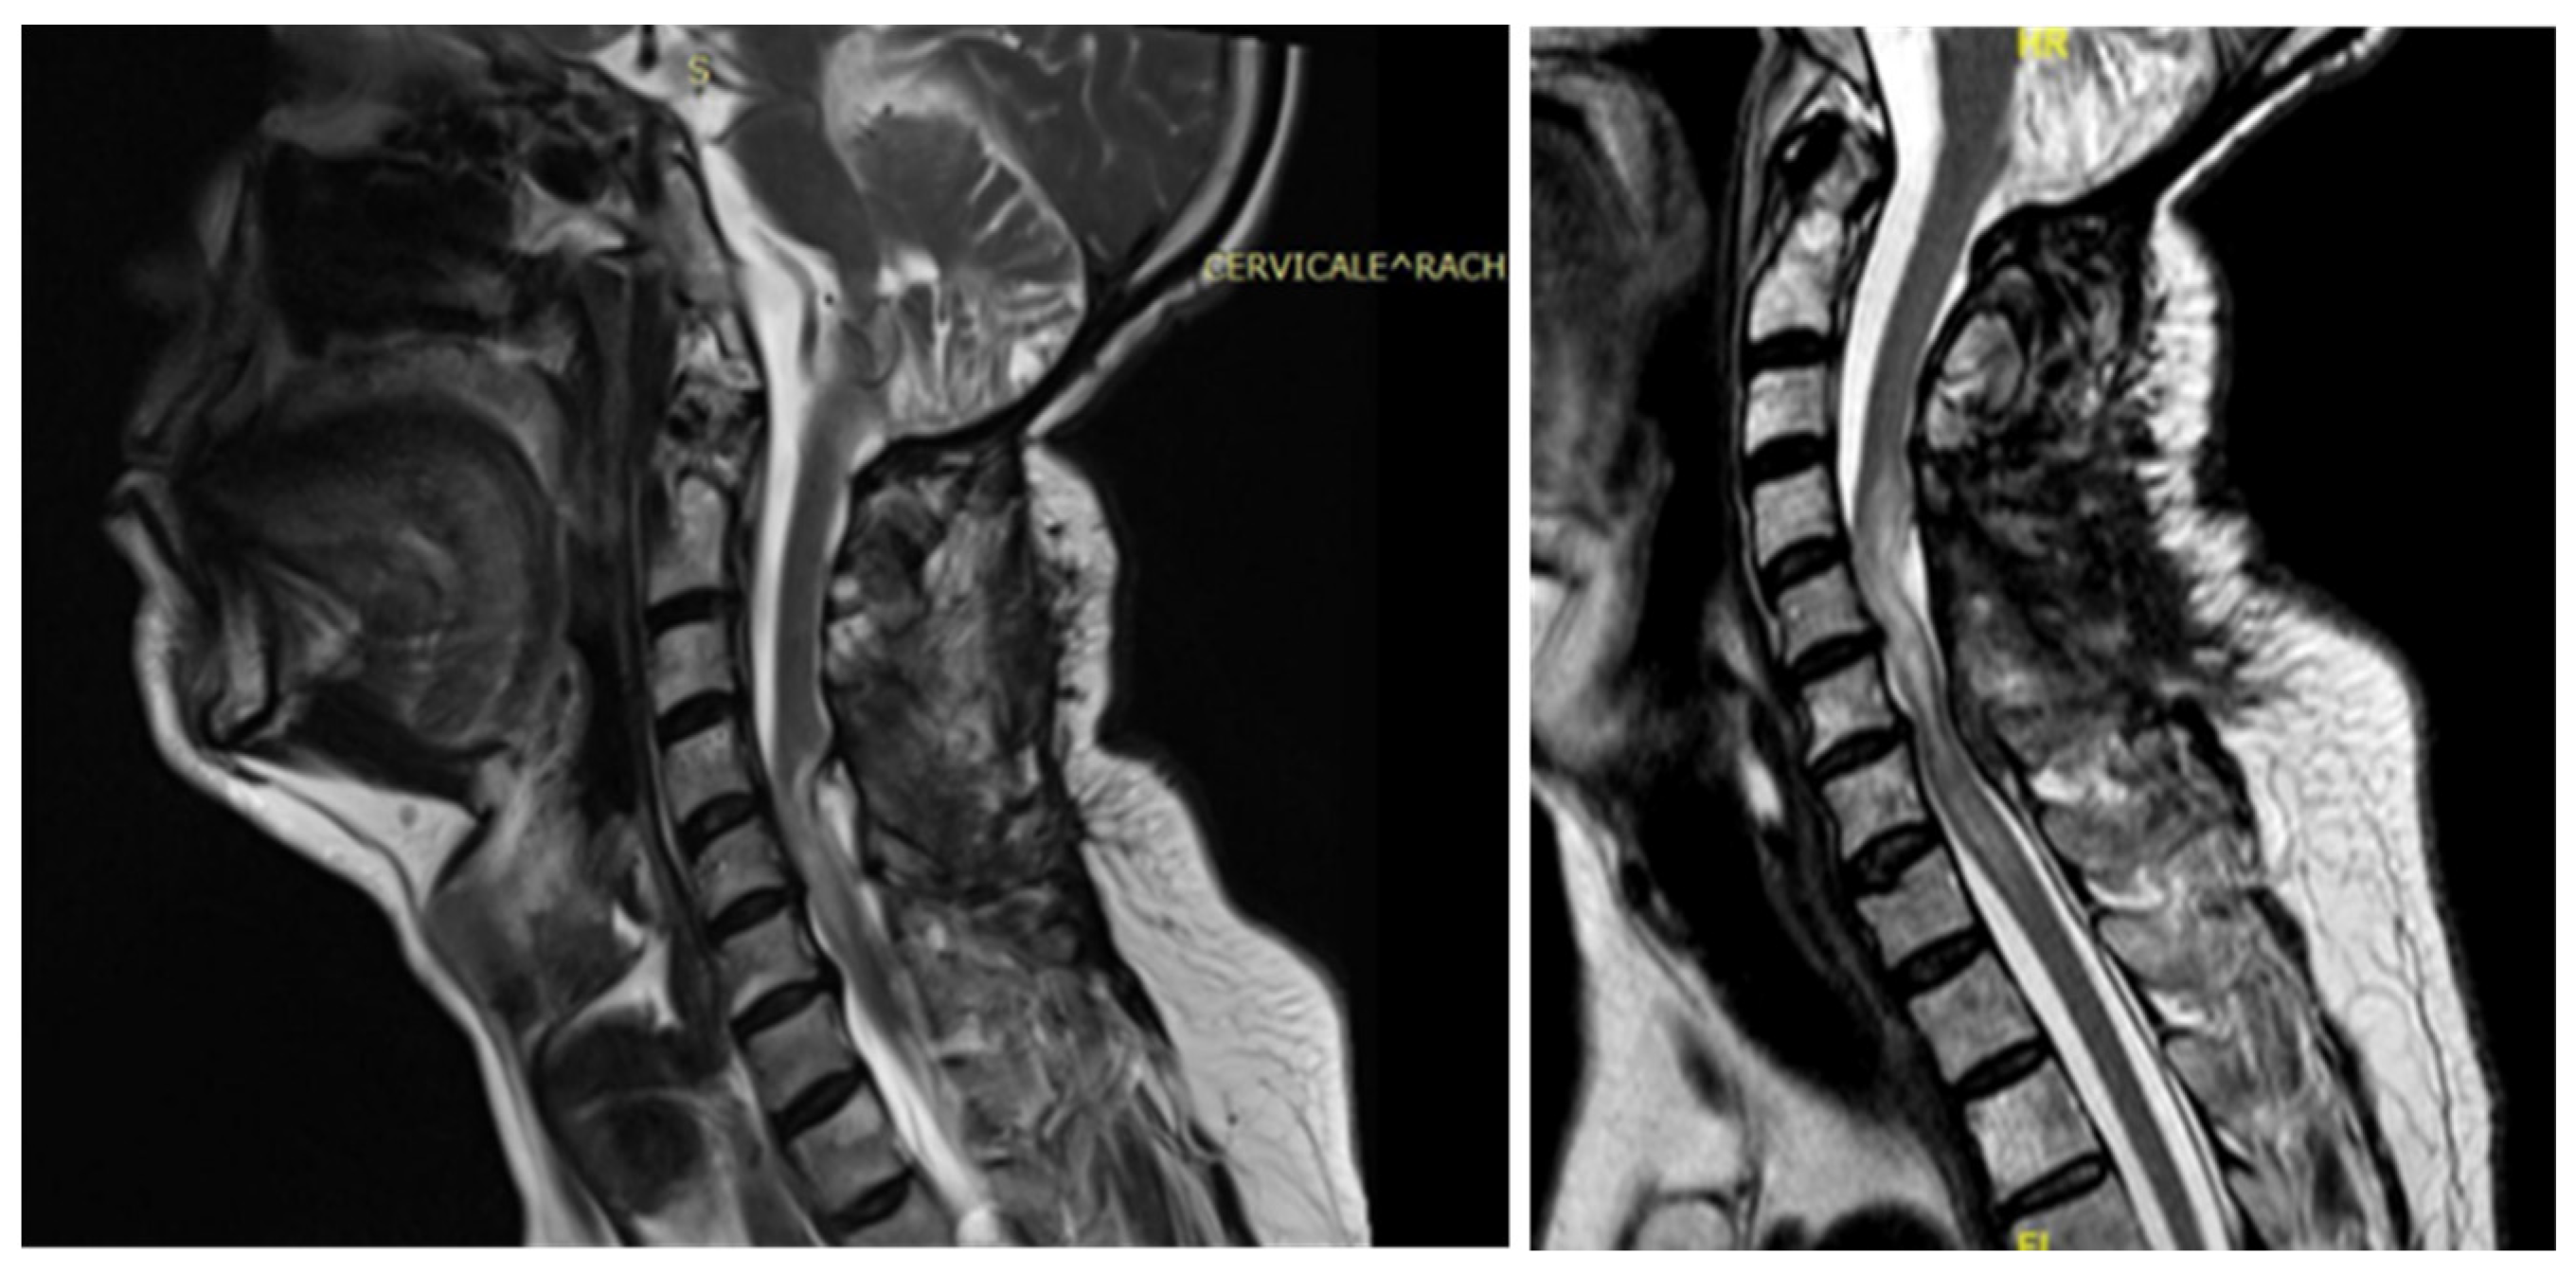

3.4.1. Case 1

3.4.2. Case 2

| Level | T12–L2 | C5–C6 | T7–T10 | T8–T9 | T8–T11 |

| Location | Intramedullary | Intradural | Intradural–Extradural | Intramedullary | Intradural |